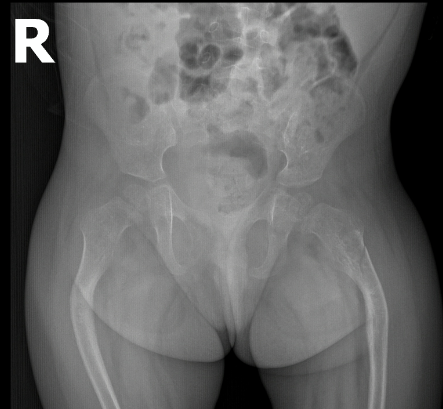

Xquang khớp háng thẳng BN gãy xương bệnh lý/tạo xương bất toàn

Xquang khớp háng thẳng BN gãy xương bệnh lý/tạo xương bất toàn